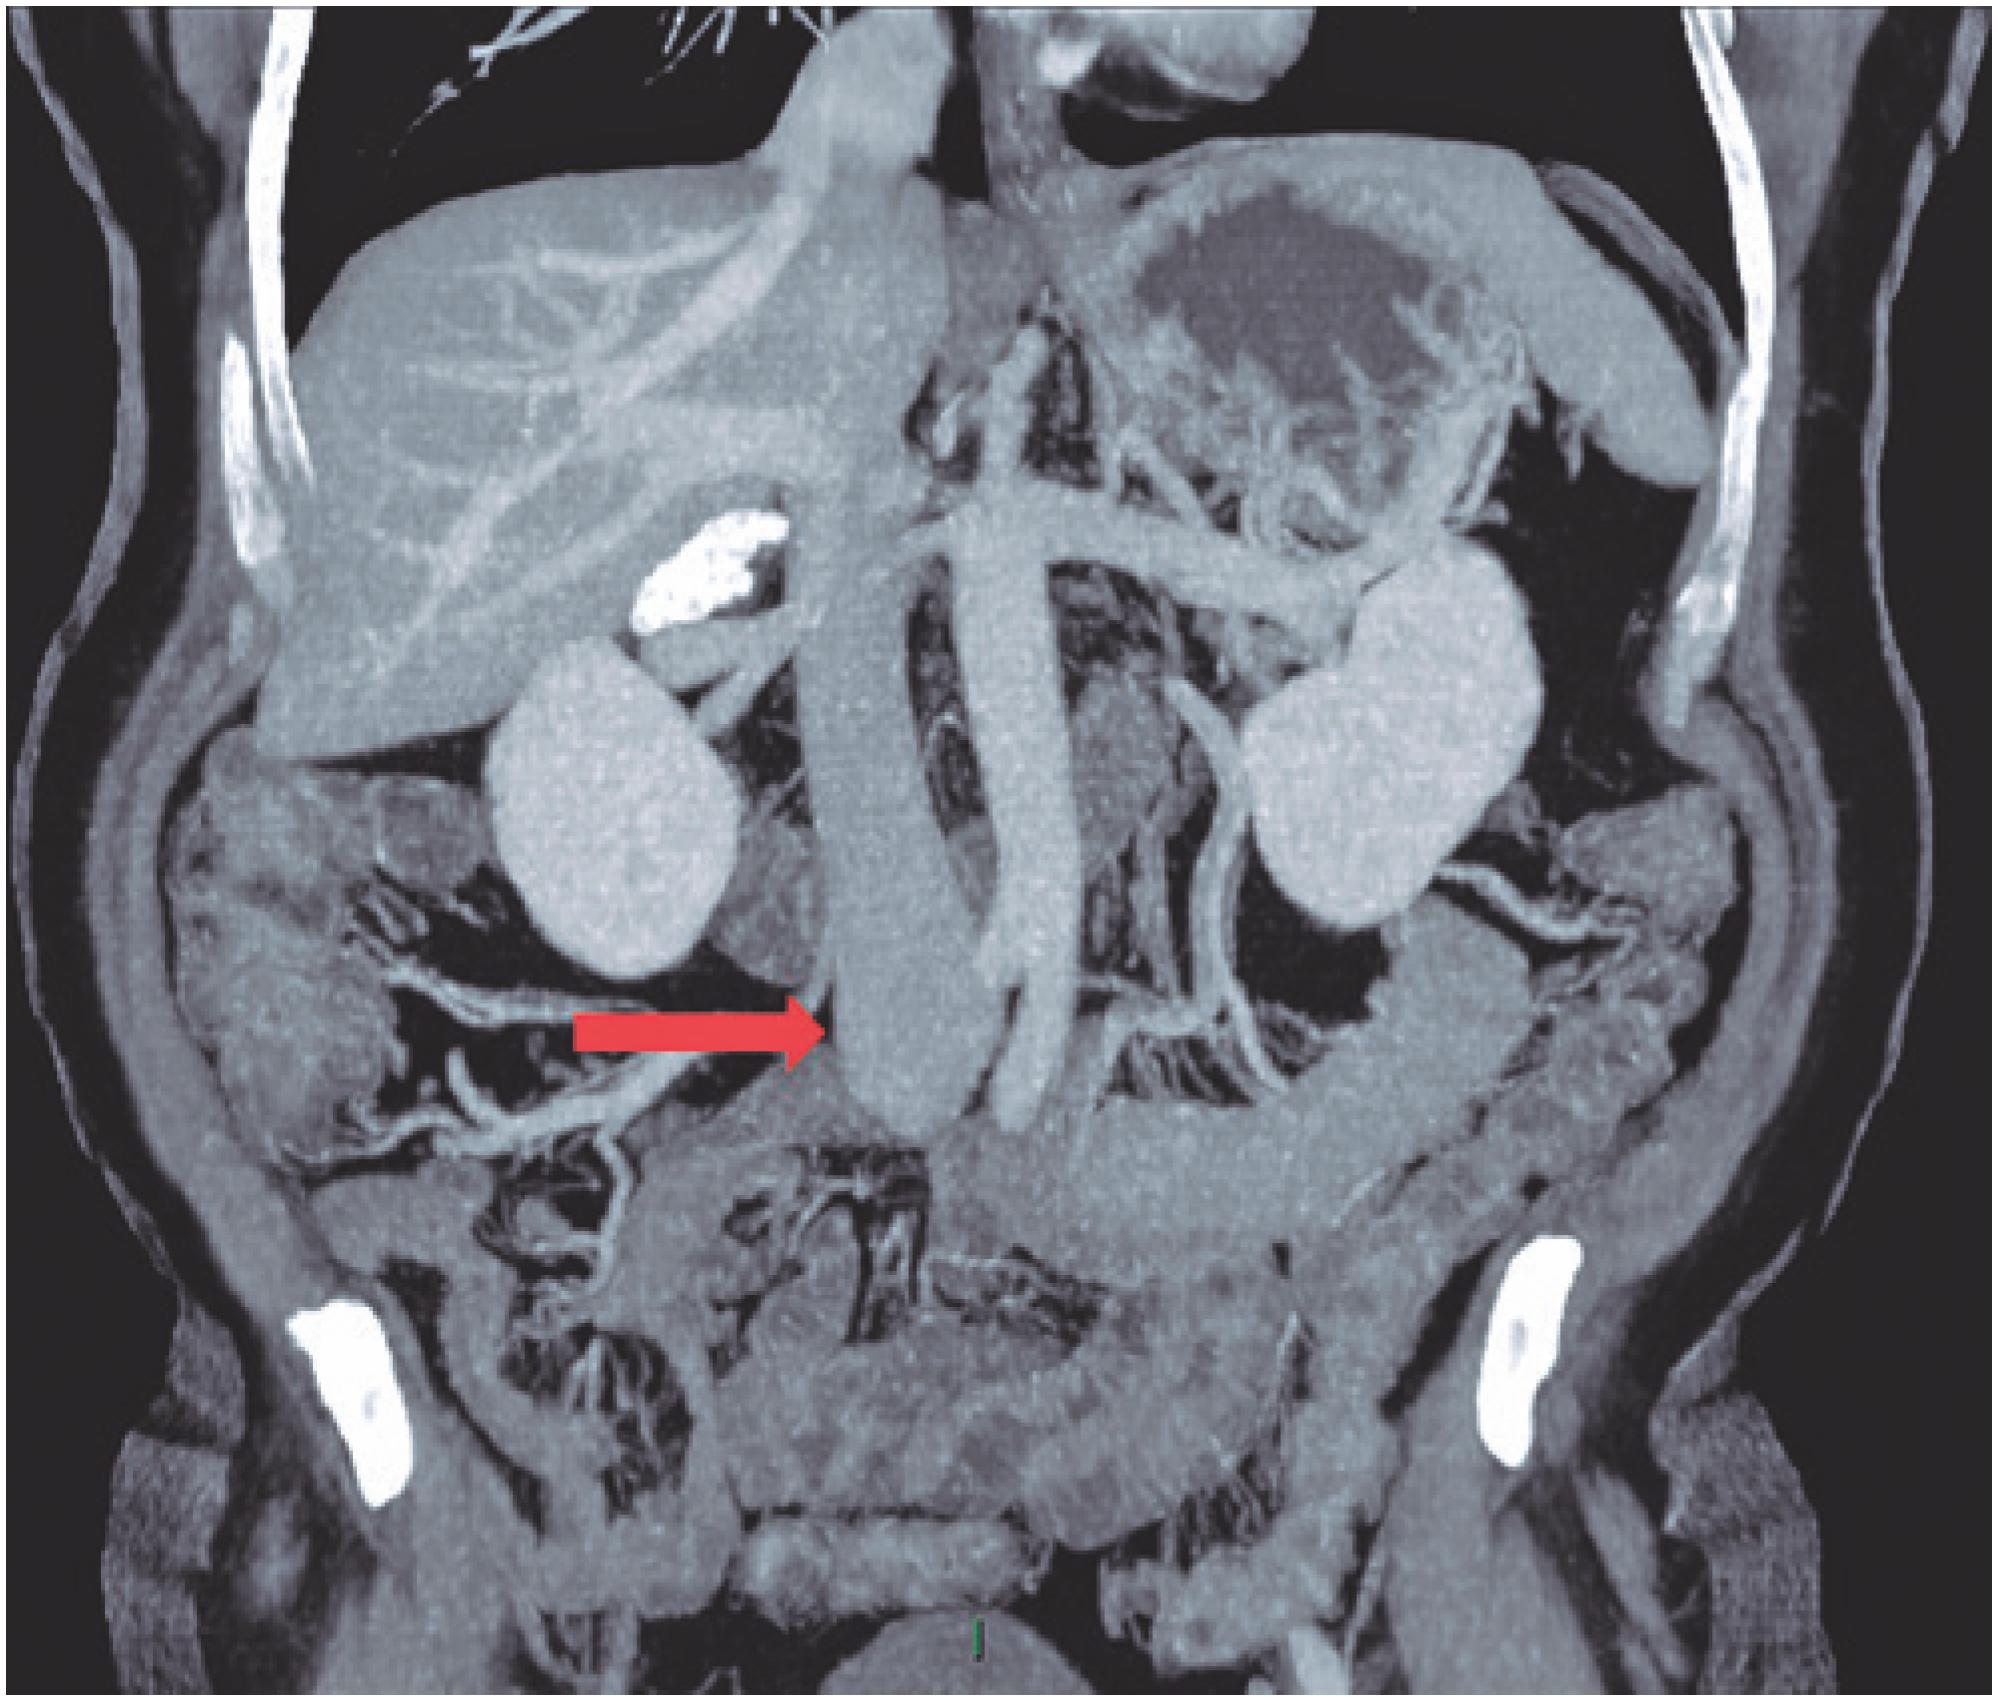

Angio‐TC. Duplicação da veia cava inferior (setas). Download Scientific Diagram